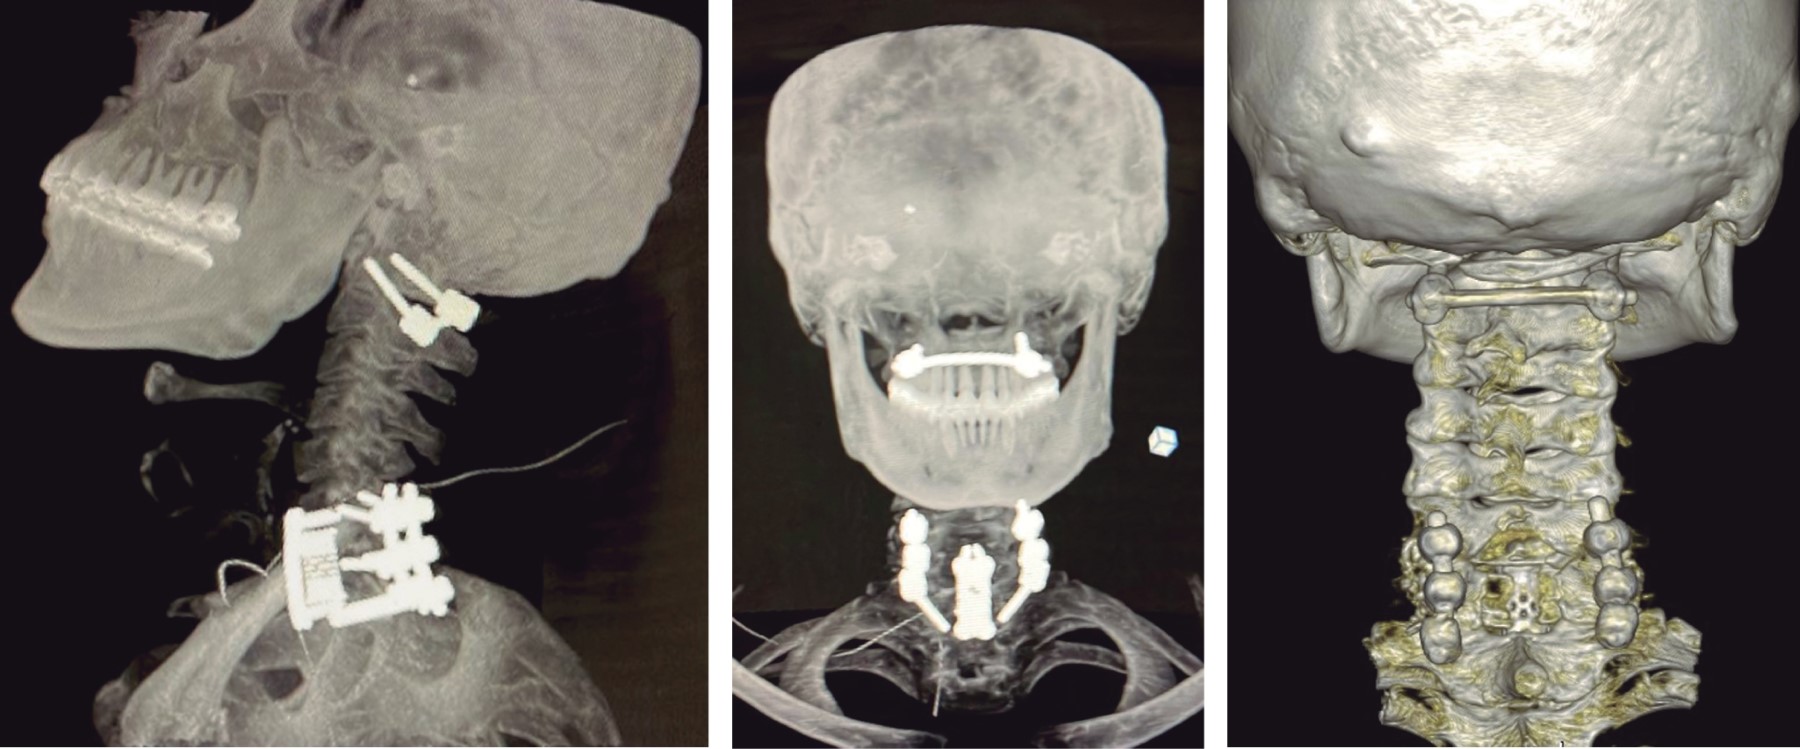

y lesión de las estructuras posteriores (Figura 4). Se realizó tratamiento quirúrgico consistente en abordaje cervical posterior, colocación de tornillos poliaxiales a masas laterales y reducción en C1 con barra moldeada transversa, instrumentación a masas laterales de C6 C7 transpedicular T1, laminectomía C7, abordaje cervical anterior corpectomía C7, colocación de malla con injerto óseo autólogo y placa cervical anterior (Figuras 5 y 6). La cirugía fue realizada en posición prono con estabilización de la cabeza. Se realizó una incisión media, los músculos paravertebrales fueron retraídos para exponer el arco posterior de C1 y apófisis espinosas de C6 C7 T1. La raíz nerviosa y arteria vertebral fueron identificadas y protegidas para evitar alguna lesión. Durante la disección, se localiza el plexo venoso de C1 C2, realizando hemostasia mediante compresión presentando sangrado considerable que; sin embargo, fue controlado. La unión del arco posterior con la masa lateral se identificó fácilmente por el trazo de fractura, pudiendo identificar y delimitar la masa lateral. El punto de entrada se localizó 3 mm lateral al término del arco posterior. Se insertaron bilateralmente dos tornillos poliaxiales número 4.0 × 22 mm con una angulación medial de 20o y superior de 30o. La fractura se redujo a visión directa, aproximando los tornillos y fijándolos con una barra moldeada bajo control fluoroscópico. Posteriormente se realiza instrumentación a masas laterales de C6 C7 y transpedicular en T1, laminectomía de C7 y colocación de dos barras moldeadas, la herida se cierra por planos y se coloca al paciente en decúbito supino; se realiza abordaje cervical anterior izquierdo, corpectomía de C7 y colocación de placa cervical anterior, se sutura por planos con colocación de drenaje, el cual se retira a las 48 horas. El tiempo de cirugía fue de 3:50 horas con sangrado de 1,000 cm3. El paciente fue extubado sin complicaciones y ningún déficit neurológico. Se da de alta a las 72 horas postquirúrgicas con uso de collarín tipo Aspen por seis semanas.